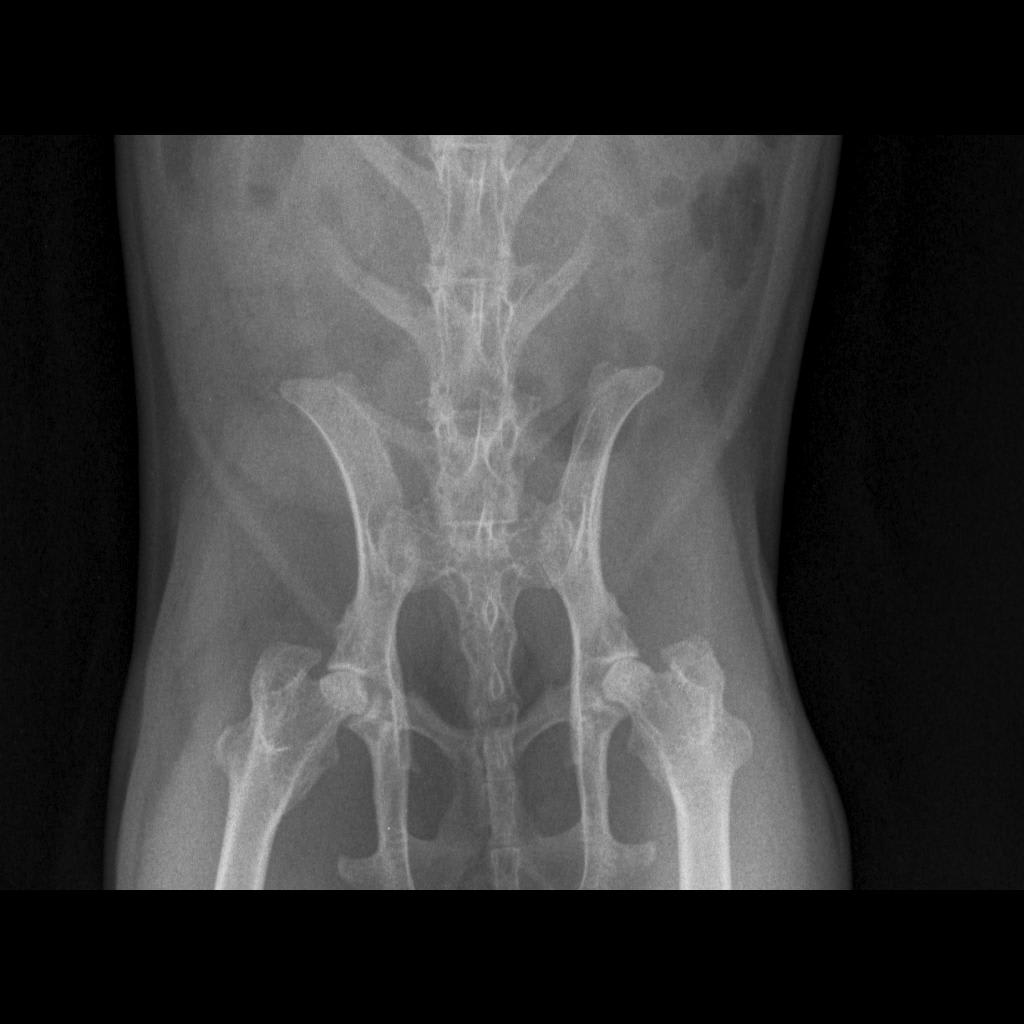

My bunny eats, but he hasn't poop for full 24h. He is lethargic, I saw him eating cecotropes, but they were dry. Yesterday, I gave him 3x simethicone 1.5ml for 3 hours, then continued 1ml for periods 3-6hr. I also gave him probiotic yr and today. Made him drink some water with apple juice and eat wet greens, but he doesn't poop. He also god flax seeds and 0.5ml virgin olive oil. Should we feed him any more, and also is it better to go give him motility drug or give him activated charcoal?

This question includes photos that may contain sensitive content. Click to view.

View more to consider that the photos may include sensitive content.